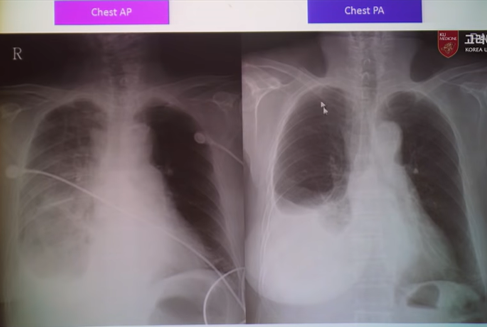

- AP view: 심장이 확대되어 보이며, 견갑골에 의해 폐야가 많이 가려지며, 횡경(Diaphragm)막이 높이 올라가 있어 폐가 좁게 나타남

- 따라서 COVID-19 선별진료소와 같이 Chest AP에서 얻은 CXR 이미지는 폐 병변을 보기에는 사실 썩 좋지 않은 경우가 꽤 있다. (Dataset 수집할 때 이러한 부분도 고려하면 좋을 듯)

- 위의 그림을 보면 같은 환자인데 Chest AP에서는 심장 size도 크고 그리고 견갑골에 의해서 폐야도 많이 가려지는 형태고 그 다음에 diaphragm도 많이 올라와 있기 때문에 PA와 비교했을 때 상당히 폐야가 좁고, 굉장히 내부의 vessel도 굉장히 engorgement(폐에서의 염증성 충혈)되어 보이는 경우가 많습니다.

- 이러한 경우, GGO 병변을 딱히 구분할 수 없거나 잘 안보이는 경우가 생길 수 도 있습니다. → 참고로 GGO는 COVID-19에서 발견되는 주요 소견 중 하나입니다.